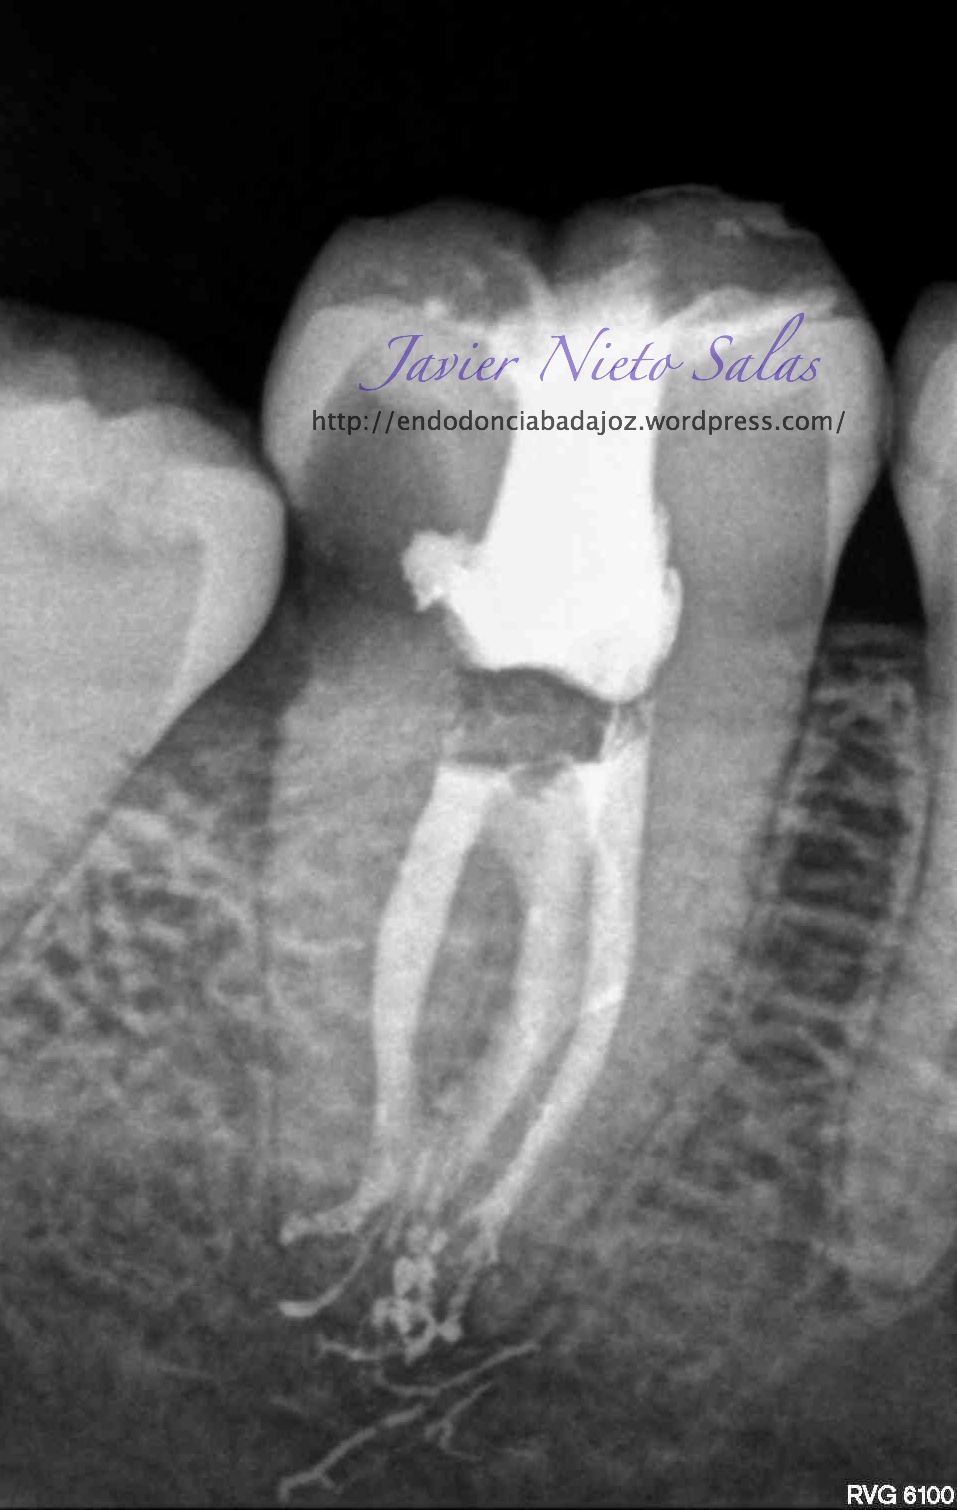

Empezaremos con el primer caso, un 4.7, se trata de una necrosis con afectación periapical.Ante las pruebas diagnósticas, nos fijamos en una fístula muy coronal, un sondaje vestibular puntual, esto nos hace pensar en un diagnóstico diferencial con un Sindrome de Diente fisurado. Sin aparente linea de fisura coronal, no vemos, con la ayuda de la magnificación, linea de fisura, lo que no nos descarta definitivamente que se trate de este síndrome de fisura, pues como ya sabemos pueden aparecer en diferentes tramos de la pieza, clasificando así los diferentes tipos.

Realizamos el tratatamiento de conductos con la sospecha del causante de la necrosis es una fractura vertical, pero no hemos podido ver la linea de fisura.

Se trataría de una cámara pulpar Tipo Ic según la clasificación por el método de Min:

El sistema de Obturación sería con condensación vertical.

(disto)                                                                     (mesio)